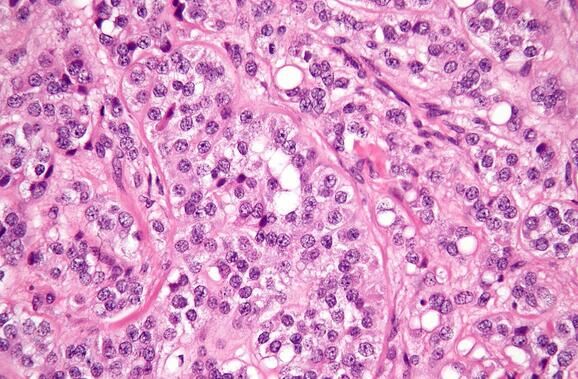

近日,一组由俄罗斯国立核能研究大学-莫斯科工程物理学院教授Viktor Timoshenko领导的物理学家和生物学家在超声的帮助下使用硅纳米颗粒识别并杀伤肿瘤,但是不损伤正常组织,相关研究成果发表在Nanotechnology上。 “我们找到了一种利用超声杀伤癌细胞的新方法,不会导致细胞大量破坏,但是可以通过纳米颗粒破坏细胞内的细胞器。”来自莫斯科国立大学的Andrey Sviridov说道。他说在硅纳米颗粒上覆盖一层高分子不会影响其声学性质,但是会产生更好的治疗效果。 最近,物理学家、化学家及纳米科学家正在开发不会损伤正常组织和器官的新型手术或治疗方法。例如研究人员已经开发了可以引入肿瘤组织并采用激光加热杀伤癌细胞的纳米颗粒,它们可以破坏癌细胞,但是不影响正常细胞,可以产生与基因治疗和特殊药物相似的效应,阻止肿瘤血管生长并饿死癌细胞。